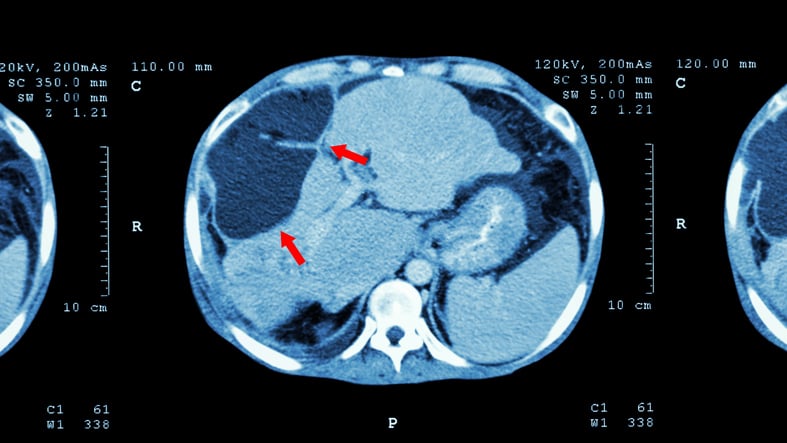

Ogni anno in Italia sono circa 13 mila le nuove diagnosi di tumore del fegato. In oltre il 90% dei casi si tratta di carcinoma epatocellulare, la forma più comune di neoplasia epatica. Quasi due terzi dei casi sono riconducibili a fattori di rischio noti quali l’infezione da virus dell’epatite C e da virus dell’epatite B. Non solo, secondo i dati dell'Associazione Italiana di Oncologia Medica, nelle aree del Nord Italia circa un terzo dei tumori del fegato è attribuibile all'abuso di bevande alcoliche.

Il trattamento varia in base allo stadio della malattia: nelle fasi iniziali i pazienti con una buona funzionalità epatica possono essere candidati all'intervento chirurgico di rimozione e addirittura ad un trapianto di fegato. Nelle fasi più avanzate invece si possono utilizzare terapie regionali come alcuni radiofarmaci, terapie a bersaglio molecolare e immunoterapia. Il tutto varia in base alle caratteristiche molecolari del tumore. La chemioterapia sistemica, invece, ha dimostrato una bassa efficacia. Quando la malattia è metastatica, la sopravvivenza a 5 anni dalla diagnosi purtroppo non supera il 10%. Ecco perchè sono allo studio diverse soluzioni terapeutiche per migliorare le prospettive dei malati.

Nello studio presentato ad ASCO gli scienziati hanno provato ad utilizzare C-CAR031, una Car-T capace di riconoscere la proteina GPC3 presente sulla superficie delle cellule tumorali del fegato e pressoché assente nei tessuti sani. L'analisi ha coinvolto 24 pazienti con carcinoma epatocellulare avanzato che non avevano risposto ai trattamenti precedenti. Dalle analisi è emerso che il trattamento, a diversi dosaggi, ha portato nel 90% dei casi ad una riduzione del tumore. Un risultato importante che pone una prima pietra verso l'utilizzo di questa Car-T. Prossimo passo sarà la valutazione dell'efficacia nel controllo della malattia nel tempo.